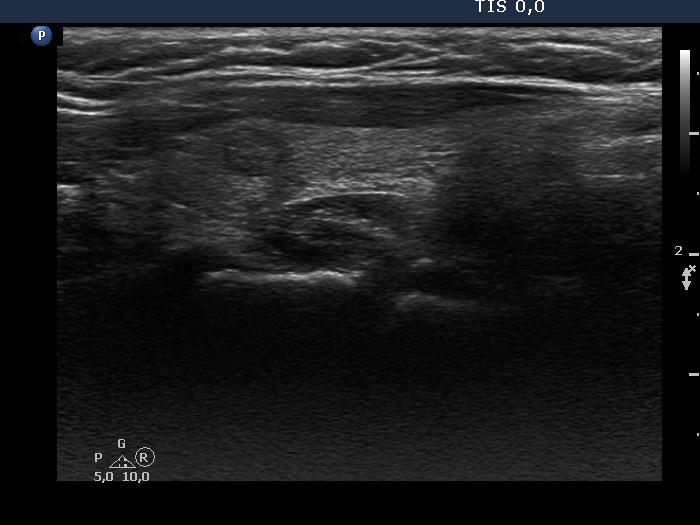

Consecutive patients with the final diagnosis of Hashimoto's thyroiditis - case 46 (1032) (ultrasonographic picture 5)

Left lobe, longitudinal view. The discrete lesion presents non-specific granulations.